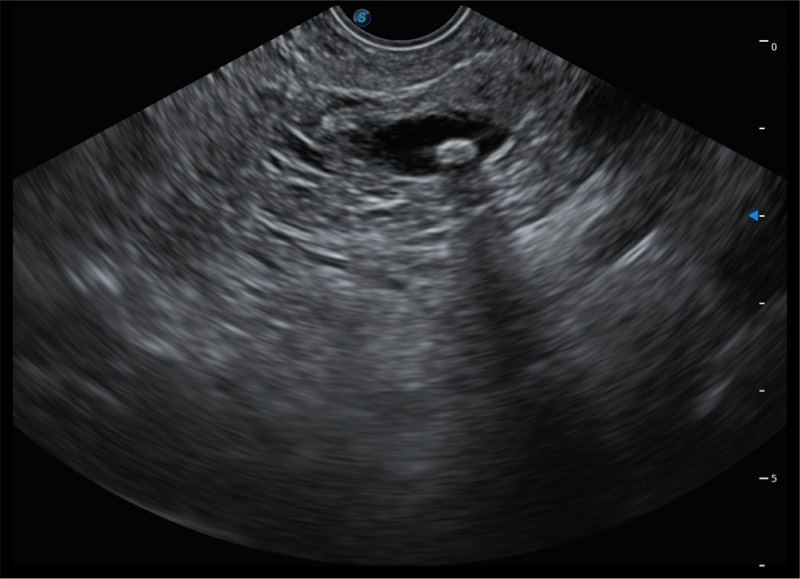

搭载百万级CMOS成像技术

及自主研发凸阵换能器,

可呈现优质的内镜和超声画面

基于二十年的超声技术积累,百老汇电子游戏官网提供了最新一代的独立超声主机,在提供高质量图像的同时满足多学科使用。具备常见多普勒技术并提供弹性成像、声学造影等高端影像技术。新一代传感器具有更强的抗干扰能力并减少图像伪影。

150°超声扫描角度